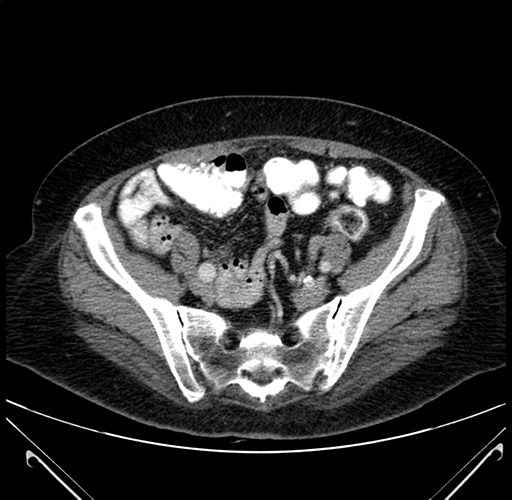

Pre-Chemo: Axial Venous

Axial Venous